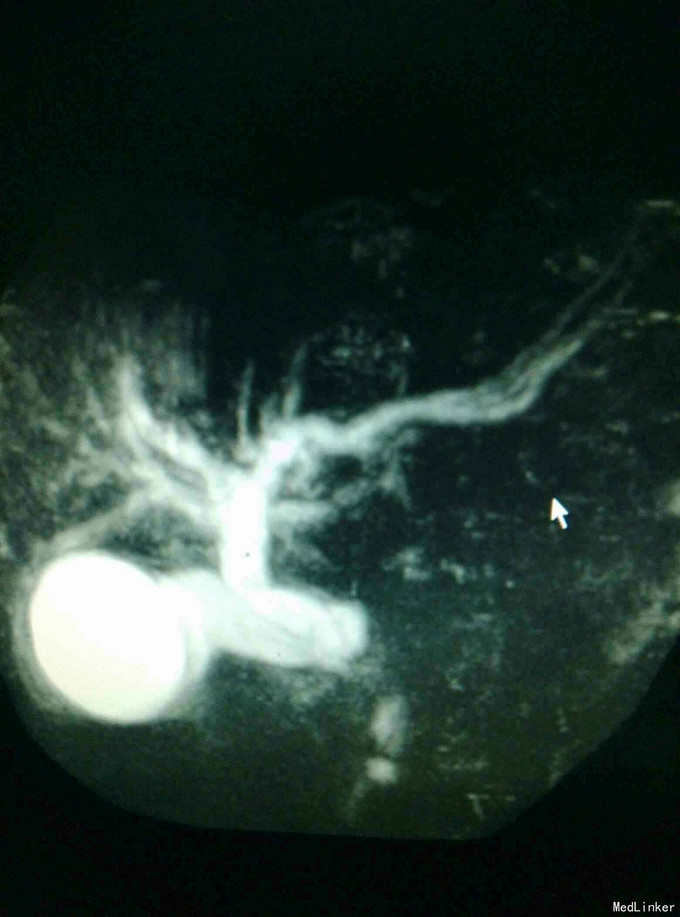

男患,74岁“发现全身皮肤及黏膜黄染2周”,2周前发现皮肤黄染,伴有纳差、厌油,无明显皮肤瘙痒,无发热、寒战,无恶心、呕吐,大便稍稀,无明显白陶土样大便,小便颜色基本正常。

全身皮肤黄染,虹膜黄染,心肺未见异常,腹部稍膨隆,肝区轻度扣击痛,Murphy症阴性。腹部查体腹部B超提示:肝内外胆管扩张,胆囊结石,胆总管下端可见低回声团。MRI如下:

梗阻性黄疸,择日进行了“胆囊切除,胆肠吻合术”,术中见胆囊及上段胆总管明显扩张,下段胆总管塌陷。

此例为下段胆总管梗阻伴胆管多发结石,ERCP切开取石适合单发或少发肝外胆管结石,而胆总管切开取石+T管引流适合单纯胆总管结石,胆肠吻合中胆管空肠吻合常用,此例选择此术式。但此术式毕竟破坏了原有结构,括约肌功能未得以保留,易诱发感染。 术后注意饮食,避免过度油腻食物,注意随访。